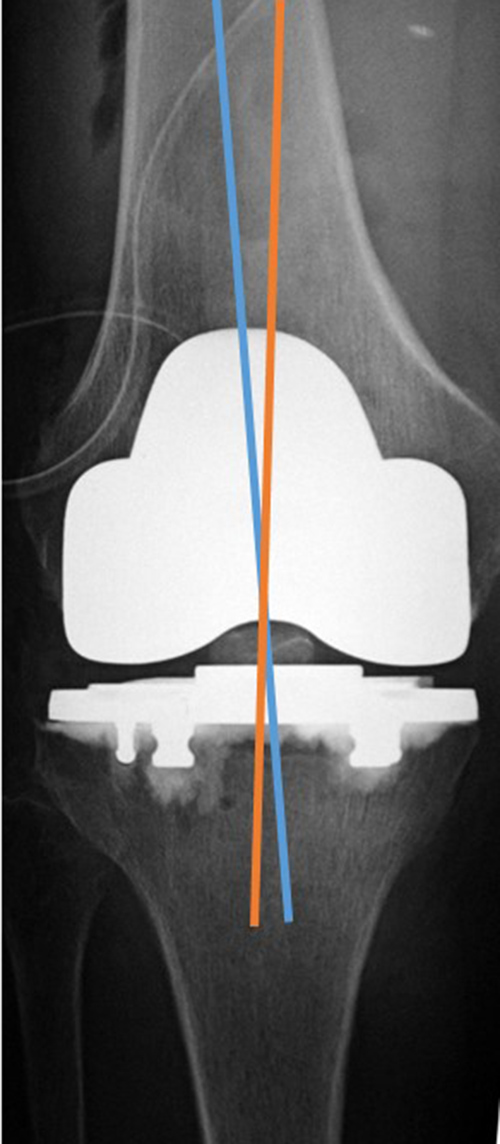

| Total Knee arthroplasty (TKA) Evaluation |

| 67 year-old woman. Postoperative images of a Biomet XPA Bicruciate Preserving TKA. Same patient as above. On the AP view (left image) the femorotibial angle is the intersection between the femoral anatomic axis (blue line) and the tibial anatomic axis (orange line). The femoral component should be centered along the femoral anatomic axis, and the tibial component should be perpendicular to the tibial anatomic axis. The femorotibilal angle should be 4-7° valgus. On the lateral view (right image) the femoral component should be roughly perpendicular to the femoral anatomic axis (orange line), and the tibial component should be perpendicular to the tibial anatomic axis (blue line) or have slight flexion (3°–6°) [posteriorly sloped]. |